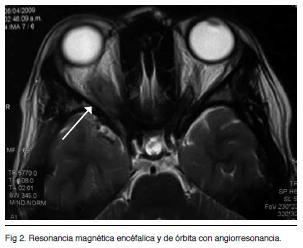

Resonancia magnética encéfalica y de órbita con angiorresonancia (Figuras 1 y 2)

Identifica un proceso sólido que ocupa el vértice de la órbita derecha. Compromete el musculo recto superior y desplaza discretamente la vena orbitaria superior. Se presenta isointenso en las secuencia T1 y T2 con realce luego de la administración del contraste i/v. La secuencia vascular, luego de la del contraste, no observó alteraciones vasculares destacables. Probable Pseudotumor orbitario o probable STH derecho.